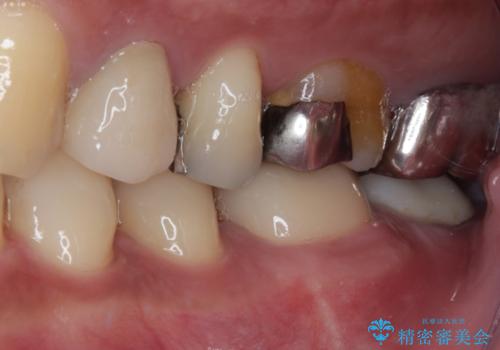

- 左下の歯が欠けてしまったとのことで来院された患者様です。

大きな銀歯が装着されており、その周りからむし歯が広がっている状態でした。

特に症状はなく、神経組織も健全な状態であったため、むし歯を全て取り切った後にフルジルコニアクラウンにて補綴することとしました。

銀歯などを使用する保険診療は、歯との境界の適合が悪く、むし歯の再発リスクが高いため、長期的な観点から使用は推奨されません。